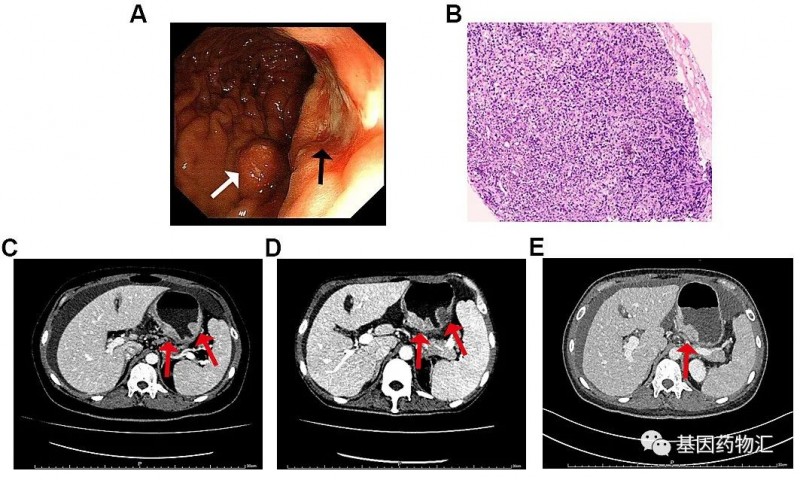

另一位47岁的胃癌患者,基本状态较差:无法行走、血小板严重降低(14×10^9/L)。CT显示患者胃底及胃体增厚,胃周、肝门、腹膜后、纵隔及双侧肺门区多处淋巴结转移,且存在广泛的全身性骨转移(右侧额骨眶上缘、双侧锁骨、双侧肩胛骨、多根肋骨、胸椎、腰椎和骶椎、骨盆骨、右侧肱骨和双侧股骨上部)。

二代测序结果提示患者存在MET扩增及MET ST7重排,微卫星稳定,肿瘤突变负荷中等(6.3个突变/Mb),分期为ⅣB期。

患者接受了对症的治疗(红细胞、血小板及促血小板生成药物输注等),并且尝试了纳武单抗治疗。但输注药物后,患者的血小板迅速下降。后患者接受了低剂量的S-1化疗,治疗3天后出现黑便和鼻粘膜出血,血小板计数继续降低。

至入院21天,患者开始出现发热、肺部感染、急性左心衰竭,病情危笃!结合患者的情况,医生最终为他选择了赛沃替尼(沃利替尼,savolitinib)方案。

令人欣喜的是,塞沃替尼方案的效果非常显著!治疗4天后,患者血小板恢复至27×10^9/L,骨痛等症状也明显开始缓解;治疗18天,患者血小板恢复至81×10^9/L,达到了出院的标准。

至治疗55天回访时,患者的血小板(188×10^9/L)、血红蛋白(111g/L)以及白细胞都恢复到了正常水平,肿瘤标志物也明显降低,CT复查胃底和体壁变薄,淋巴结缩小,骨髓图片显示无转移性癌细胞。根据标准,患者已经达到了部分缓解。

病危之际尝试新药,这位患者终于重获生机!

案例三、三线治疗,再达缓解[3]

另一位接受了赛沃替尼治疗的患者,39岁女性,Ⅳ期低分化胃腺癌(cT4aN3M1),双侧卵巢转移,胃周、腹膜后和肠系膜区域广泛淋巴结转移。IHC显示HER2和PD-L1 CPS阴性,二代测序提示MET扩增、微卫星稳定、肿瘤突变负荷3.95个突变/Mb。

患者一线接受了纳武单抗联合S-1和奥沙利铂治疗,二线接受了白蛋白紫杉醇治疗;三线治疗时,考虑到MET扩增,患者尝试了塞沃替尼治疗。

至治疗8周时,患者的症状缓解非常明显,肿标明显降低,达到了临床部分缓解的标准,连体重都增加了10公斤!